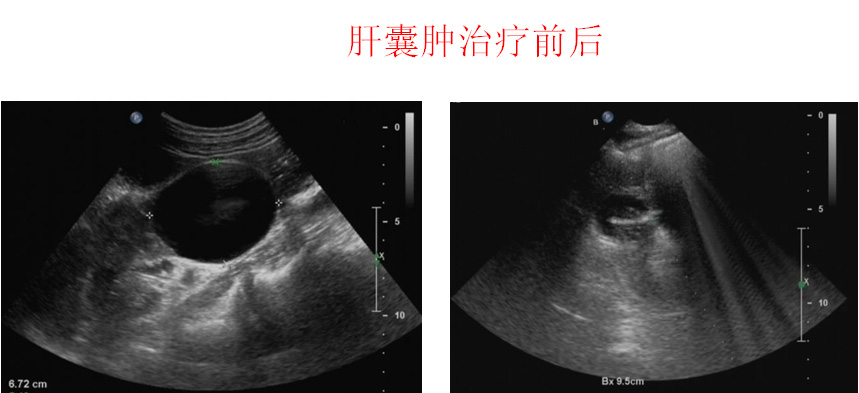

包括:甲状腺细针穿刺检查,超早期诊断甲状腺肿瘤;全身各部位占位性病变的穿刺活检,得出病理诊断结果;肝脏、肾脏囊肿酒精硬化治疗;各部位脓肿的穿刺治疗,非手术解决患者的痛苦;各部位积液超声引导下抽吸治疗,彻底、无风险;超声引导下置管引流术,瞬间解决病人痛苦; 良恶性肿瘤射频、微波消融治疗,达到手术效果;乳腺肿瘤微创治疗术,引用四维定位技术,快速、准确切除乳腺肿瘤,术后不留瘢痕,满足美容要求。甲状腺肿瘤消融治疗,更是治疗肿瘤的同时,没有瘢痕,保留您颈部的美丽。